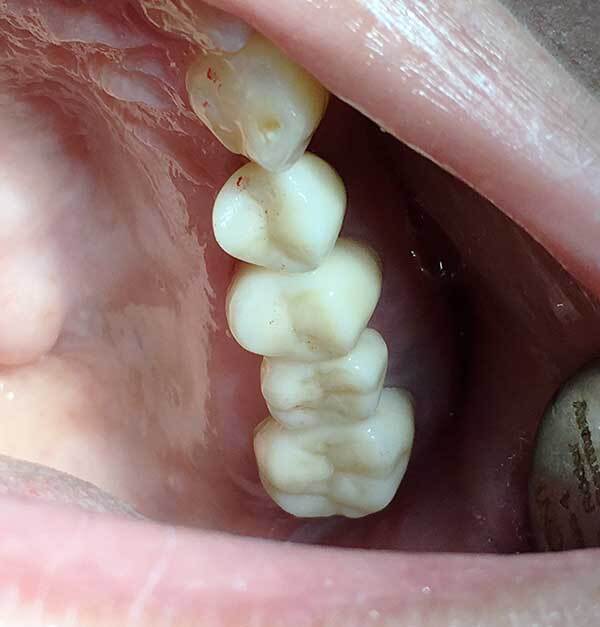

顔面外傷、歯科救急

当院唯一といってよい強みのある分野です。転倒などでの顔面、頭部外傷に関して対応可能です。頭蓋内血腫、外傷性クモ膜下出血の否定をされたうえで受診してください。脱臼歯、顔面の挫創に関しても縫合などの処置可能です。

日々、救急医として高エネルギー外傷などを対応しているため対応可能です。

また骨折などに関しては適宜入院可能な口腔外科病院に紹介いたします。

上の症例は救急受診されたお子さんの顔面外傷ですが、緊急受診し創部処置を行い即時ワイヤー固定と脱臼した歯の再植術で無事失活せず保存できました。また顔面、口腔内の外傷に関しても傷を残すことなく治癒することができました。当然全身状態、Vitalチェックを行い医科的な問題はないと考えたうえでの対応です。これは歯科医では対応不可能な部分です。救急医としての特性を生かしたものといえます。